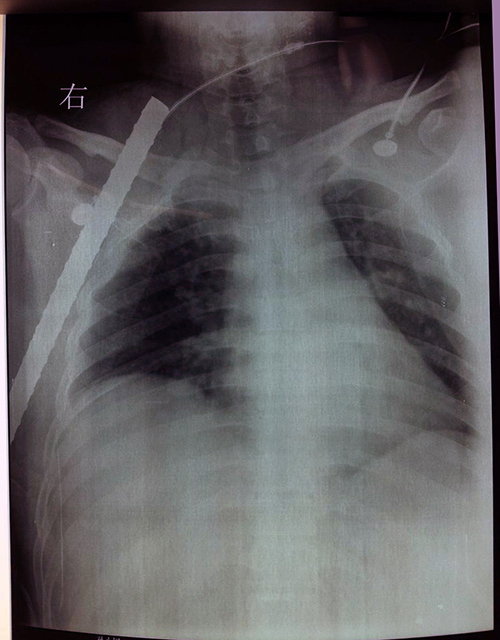

一例钢筋穿胸患者在省人民医院急救成功

就在20个小时前,患者正在手术室里紧急抢救,一根拇指粗的螺纹钢筋经右腋窝、胸壁外侧达颈根部,突破层层血管和神经,深深地扎入患者体内约35cm。副主任医师李洪波介绍,右上肢附近有诸多血管和神经,如腋动静脉、锁骨下动静脉、颈外动静脉和臂丛神经等,血液循环非常丰富。“钢筋压迫的都是近心大血管,一旦受损,后果不堪设想”他介绍到。

钢筋扎入体内没有损伤大血管,对患者来说实属幸运。但是如何将钢筋取出又不损伤受压迫的血管对医师来说是一大考验。经过会诊,省人民医院心胸外科杨文凯副主任医师和运动医学院李洪波副主任决定为患者行“剖胸探查+右侧锁骨断开复位钢板内固定术”。李洪波松解开颈部的锁骨、肌肉组织,显露出颈根部的臂丛神经、颈外动静脉、锁骨下动静脉,游离出钢筋,保护好血管和神经,杨文凯将胸壁外侧清理疏通,后万分谨慎地将钢筋缓缓抽出,手术取得了成功。整个手术大约持续了3小时。